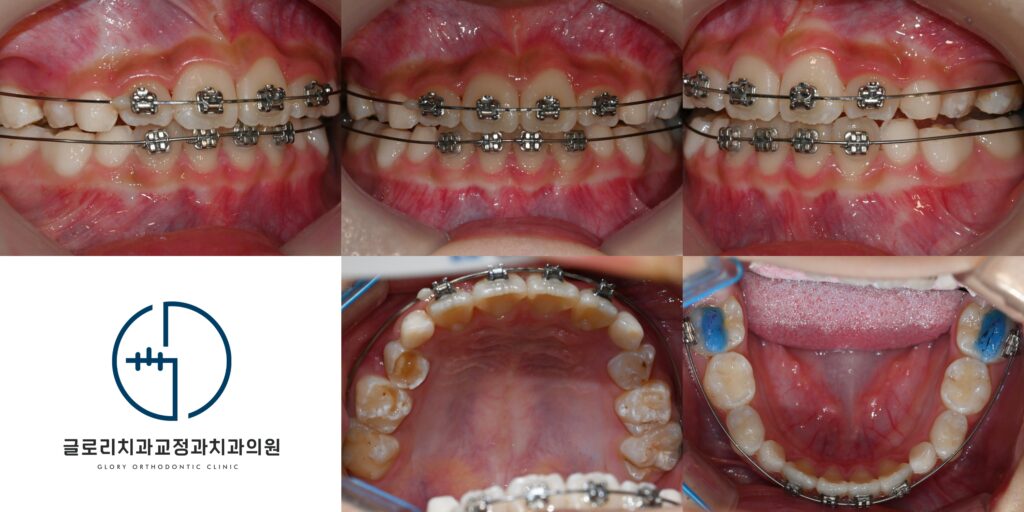

투바이포 교정으로 앞니 배열

악궁 확장이 어느 정도 진행되면 투바이포 교정을 통해 앞니를 가지런하게 배열합니다.

투바이포(2×4 appliance)는 위턱 앞니 네 개와 양쪽 첫째 큰어금니에 브라켓을 부착하는 방식입니다.

전체 치아에 장치를 붙이지 않고 필요한 부위만 선택적으로 교정하는 방법입니다.

이 방식은 혼합 치열기 아이에게 적합한 1차 교정 방법으로 앞니 공간 확보와 배열에 효과적입니다.

상악골 확장 으로 공간을 만들고 투바이포로 앞니를 정렬하는 순서로 치료가 진행된다면 덧니 개선을 기대할 수 있습니다.

치료기간 : 24.01.18 ~ 25.04.24